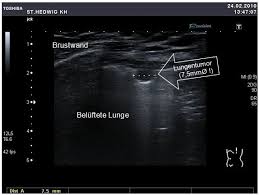

Pneumothorax Sonographie / Http Www Agnotarzt Berlin De Media Sym2013 Notfallsonographie Pdf

Ultraschall In Der Notfallmedizin Pdf Free Download